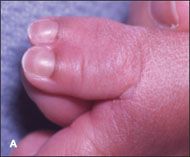

Complete duplication of the left thumb in a baby boy was noted at birth; a radiograph of the thumb showed 2 proximal and distal phalanges with 1 first metacarpal bone (A and B). He also had fusion and incomplete bony duplication of the right thumb; a radiograph of this digit showed normal proximal and distal phalanges plus a small tiny bony remnant of the proximal and distal phalanges of an accessory thumb (C and D).

The infant had no other apparent abnormalities. He had been born at term after a normal pregnancy and uncomplicated delivery. The mother had 2 sisters; each had 1 child with ulnar polydactyly-nubbin accessory digits on the little fingers.